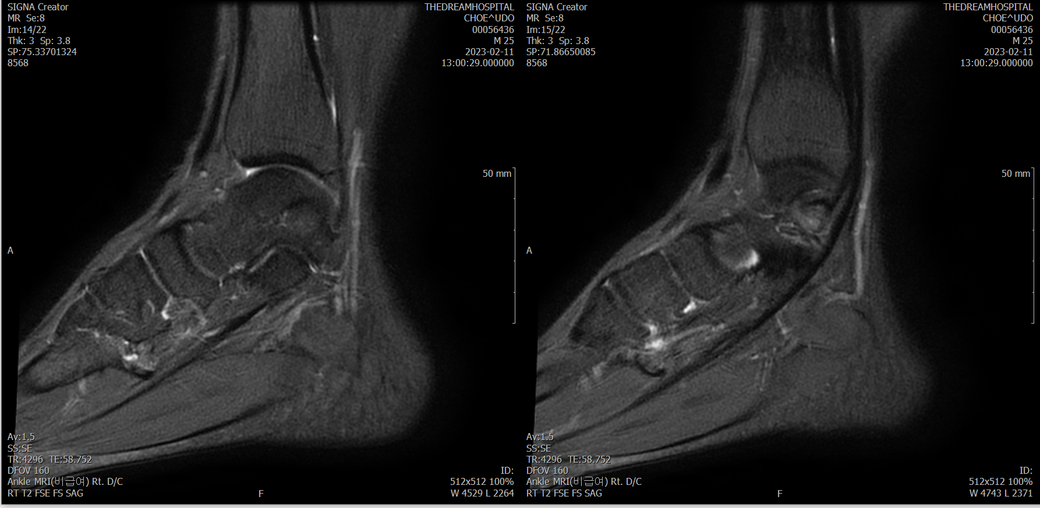

오른발목 mri 전체사진입니다. 제가 병원을 갈수없는상황인지라.... 봐주시면 감사하겠습니다.

엑스레이에서는 문제가 없다고 하여 오른발목 mri촬영했습니다.

우선 전반적으로 봤을 때 큰 이상은 없어보입니다.

전거비인대 등도 저명한 손상은 없는 것 같아 보이지만, 어느 부분의 통증 등으로 인해 촬영을 하셨는지 말씀을 해주신다면 보다 정확한 병변파악이 가능하겠으며, 병원에서 판독이 완료되신다면 전화 등으로 문의를 해보시는 것이 좋겠습니다.